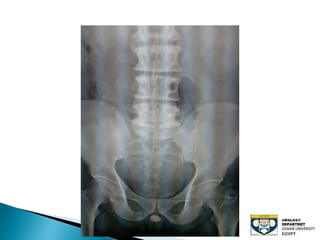

The document discusses urinary tract stones, detailing their types, causes, symptoms, and diagnostic methods. It highlights the risk factors such as infections and obstructions, with men being more commonly affected. Treatment options include various surgical methods, particularly for managing bladder outflow obstruction and lithiasis.